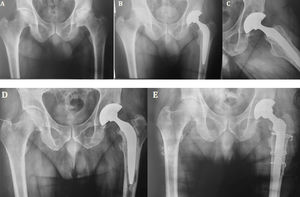

El grupo A (cementado) presentó el mayor porcentaje (73,3%) de cotilos con signos de radiolucencia y el grupoB (híbridos) presentó la mayor tasa de vástagos con signos de radiolucencia (78,2%), representando una diferencia estadísticamente significativa al realizar la comparación entre los tres grupos (p<0,001). Con respecto al análisis de la calidad de cementado, no observamos diferencias significativas entre los gruposA yB (p=0,17) (tabla 4) (fig. 2).

Paciente femenina de 48 años. A)Proyección AP preoperatoria: se observa coxartrosis de cadera izquierda. B-C)Reemplazo total híbrido, control postoperatorio inmediato. D)Control de los 14años: evoluciona con aflojamiento del componente femoral. E)Revisión a vástago de fijación distal con osteotomía femoral extendida.